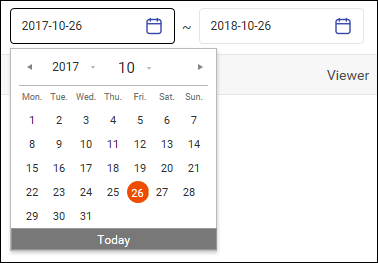

用户可以搜索患者以查找相关 DICOM 图像和相关信息。

搜索患者